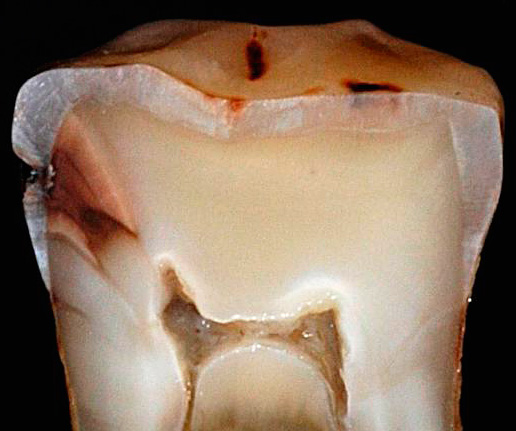

Immagini della polpa del dente:

La pulite è una reazione infiammatoria del tessuto polmonare ("nervo" dentale), che si verifica in risposta a un fattore irritante, esterno o interno. La polpa è un tessuto molle trafitto da vasi e nervi. Ci sono molte cellule nervose al suo interno, motivo per cui il mal di denti è considerato uno dei più potenti.